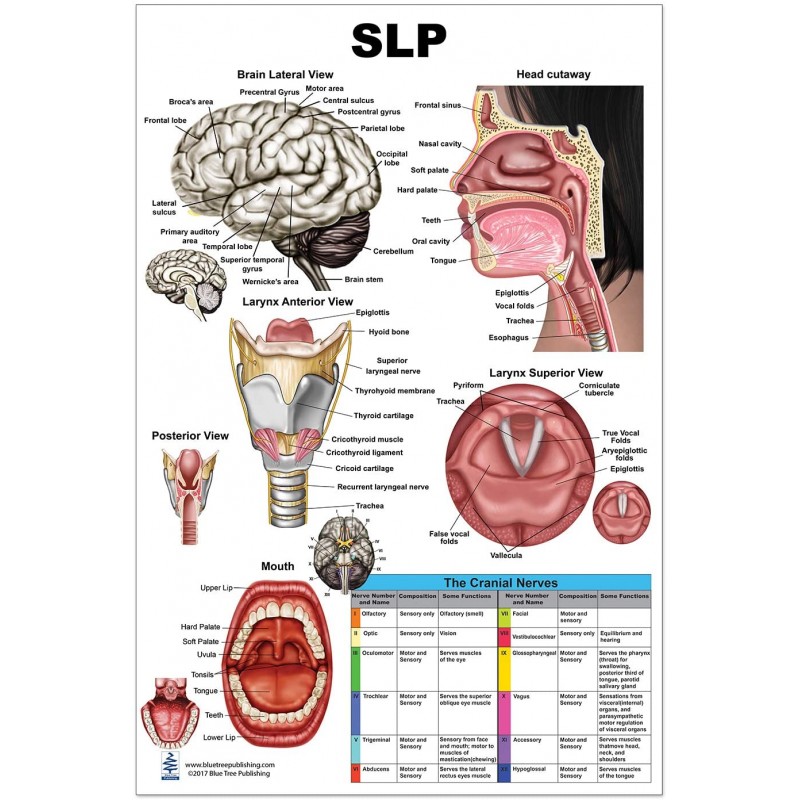

The SLP Large Poster illustrates anatomy of speech language pathology

The SLP Large Poster illustrates anatomy of speech language pathology

The SLP Large Poster illustrates anatomy of speech language pathology